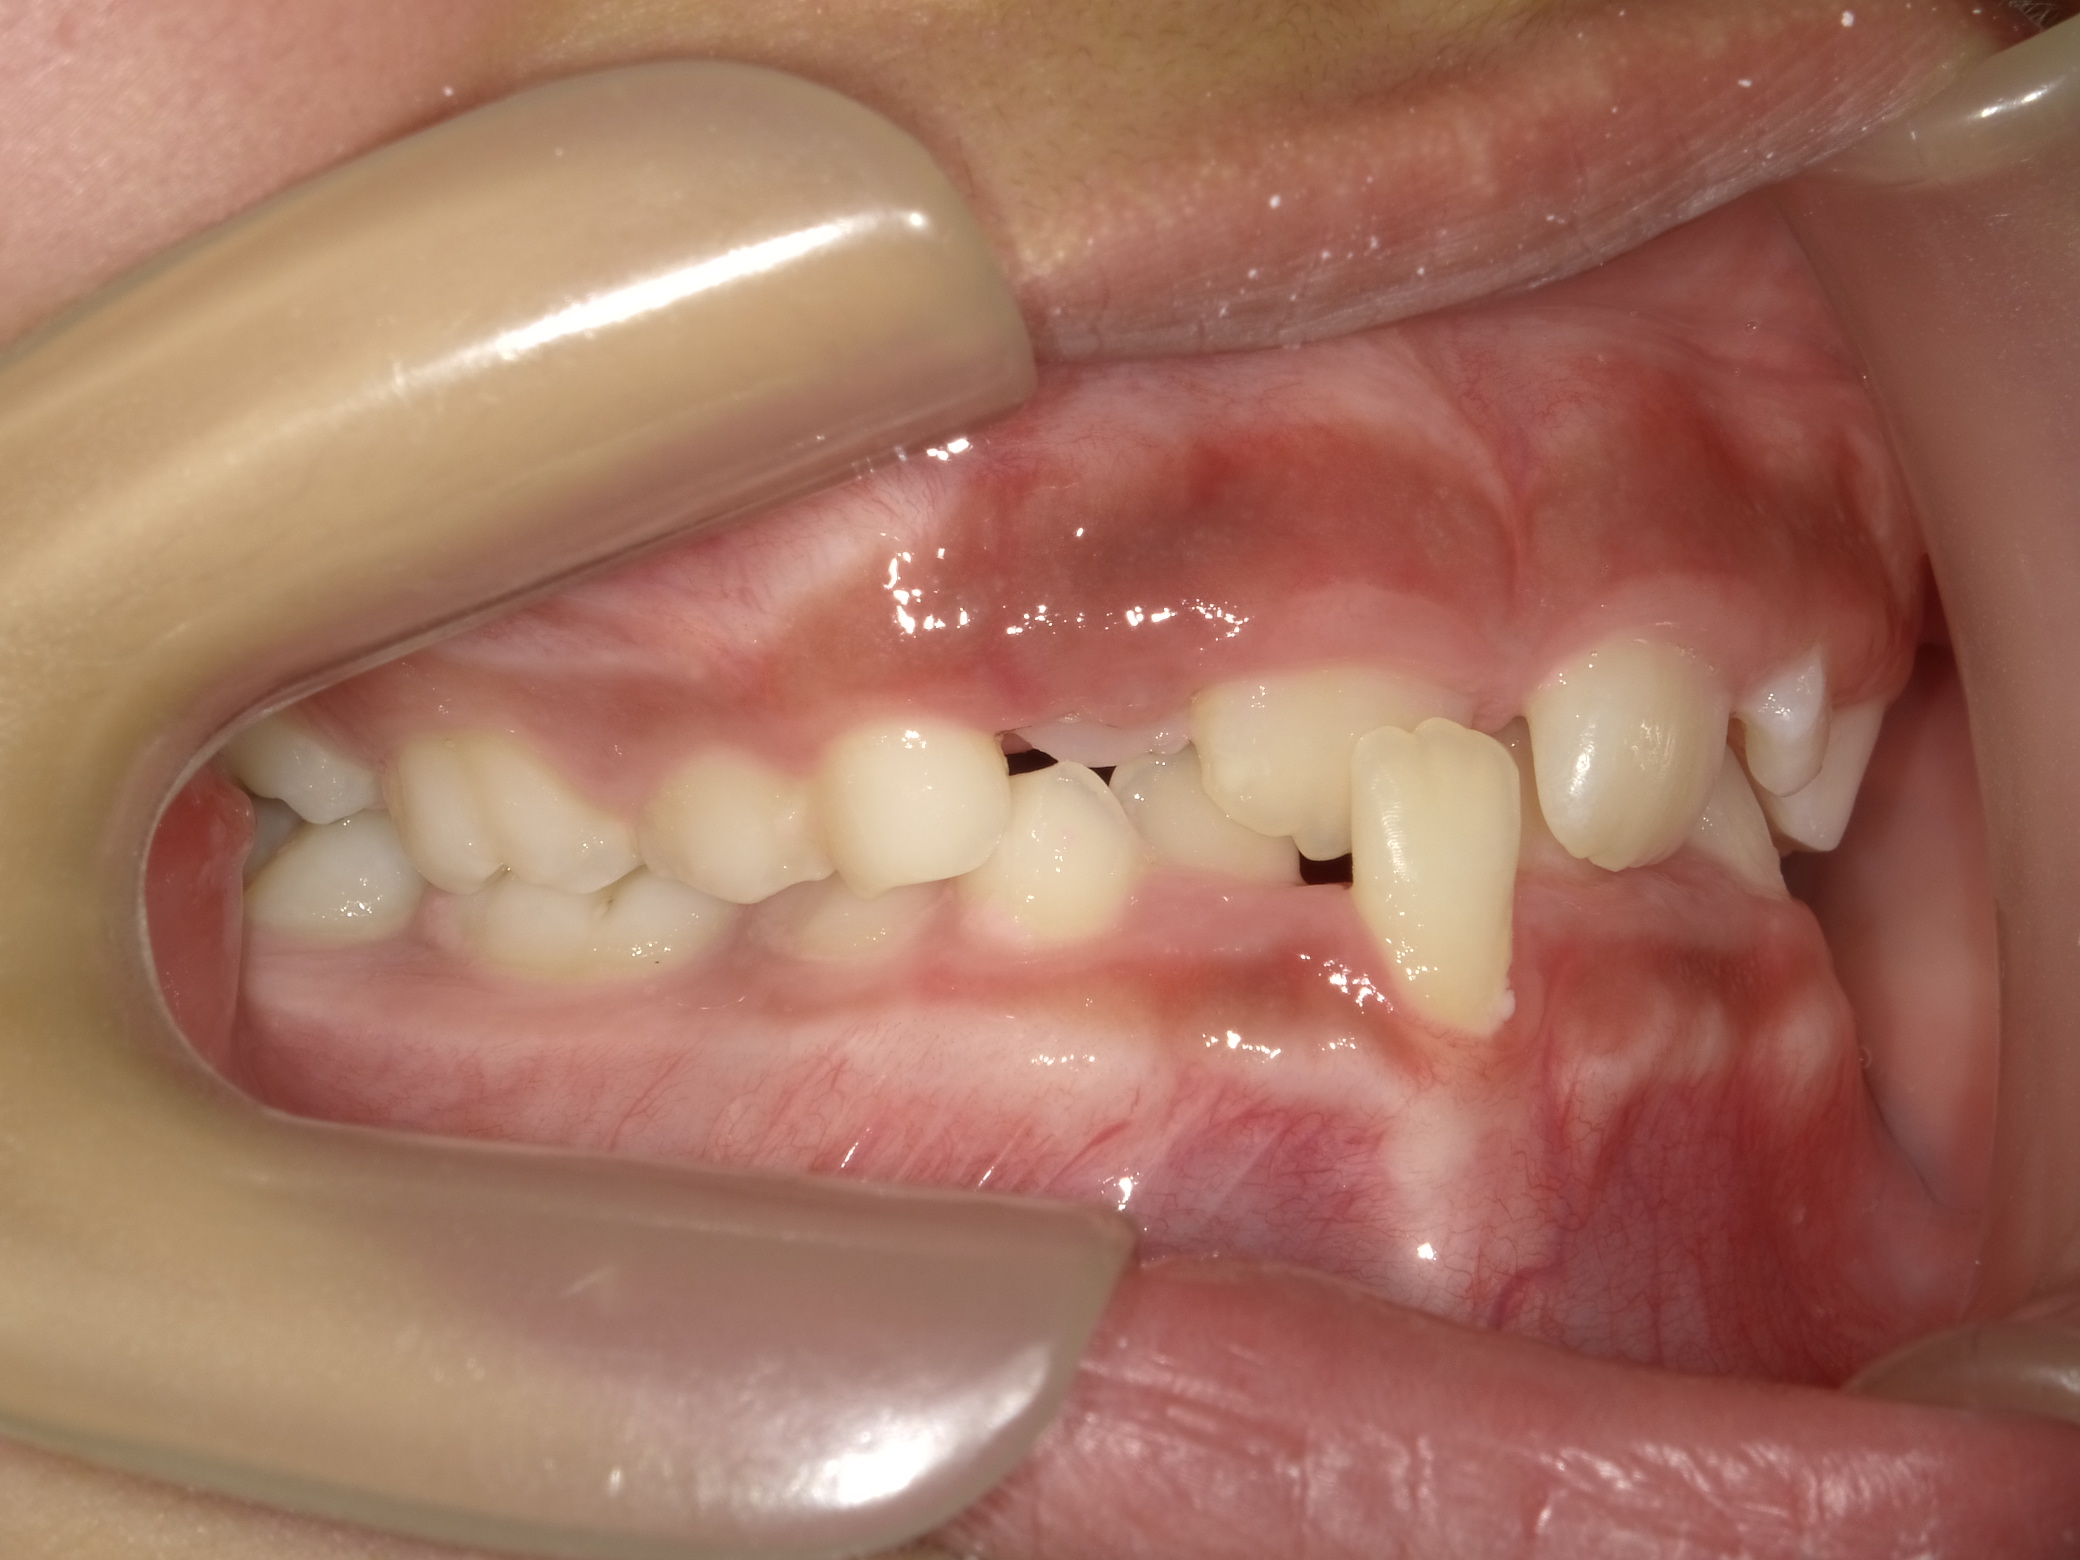

| 症例分類 | 交叉咬合 |

|---|---|

| 主訴 | 前歯がずれて咬んでいる |

| 年齢 | 9歳5ヶ月 |

| 性別 | 女性 |

| 抜歯部位 | なし |

| 使用装置 | 拡大装置、上顎前歯部のセクショナルアーチ装置、取り外し式保定装置 |

| 治療期間 | 1年2ヶ月 |

| 費用 | 相談料0円、検査料50,000円 動的矯正治療費330,000円 調整料6600円×15回分 保定装置料0円 |

| リスク・注意点 | 個々の歯の大きさに対して顎が小さく、歯が並ぶスペースが不足したために交叉咬合が生じています。これらを改善するために、幅の狭搾している歯列を側方に拡大した後、前歯を排列しました。

歯の動き方には個人差があり、予想された治療期間が延長する可能性があります。 治療中は矯正歯科装置が歯の表面に付いており、歯が磨きにくくなるため、むし歯や歯周病が生じるリスクが高まります。ハミガキを適切に行ってお口の中を常に清潔に保ち、さらに、かかりつけ歯科医に定期的に受診することが大切です。 矯正歯科装置の使用状況、定期的な通院など、矯正歯科治療には患者さんの協力が必要であり、それらが治療結果や治療期間に影響します。 治療の経過によっては当初予定していた治療計画を変更する可能性があります。 保定装置の装着時間が十分確保できない場合、歯並びや、咬み合せの「後戻り」が生じる可能性があります。 上下両側第二大臼歯の萌出を観察する必要があります。 |